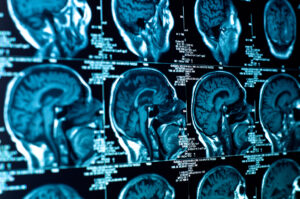

Brain tumour immunotherapy, particularly DCVax is gaining an increasing amount of media coverage and interest. We are seeing a growing number of calls to our brain tumour support helpline about DCVax and brain tumour immunotherapy. Here we shed some light on the current state of play for one particular brain tumour immunotherapy trial and some recently published results.

DCVax is looking promising but currently the trial is closed and is in set up for the next phase. It is going to be a while before this treatment is accessible. And when it is? Well, it will only be suitable for a minority who fulfil the trial criteria and even then some of these patients will not succeed. The results make interesting reading; this is some of what we know: